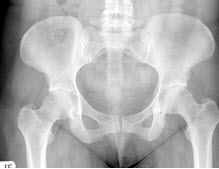

141、单项选择题

女,根据其正常骨盆影像图像,判断其最可能的年龄()

A.53岁左右

B.13岁左右

C.73岁左右

D.33岁左右

E.63岁左右